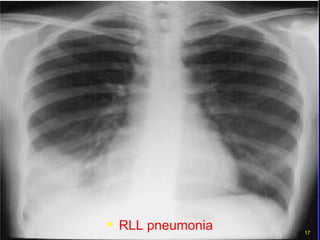

RLL pneumonia

Right Lower Lobe Pneumonia